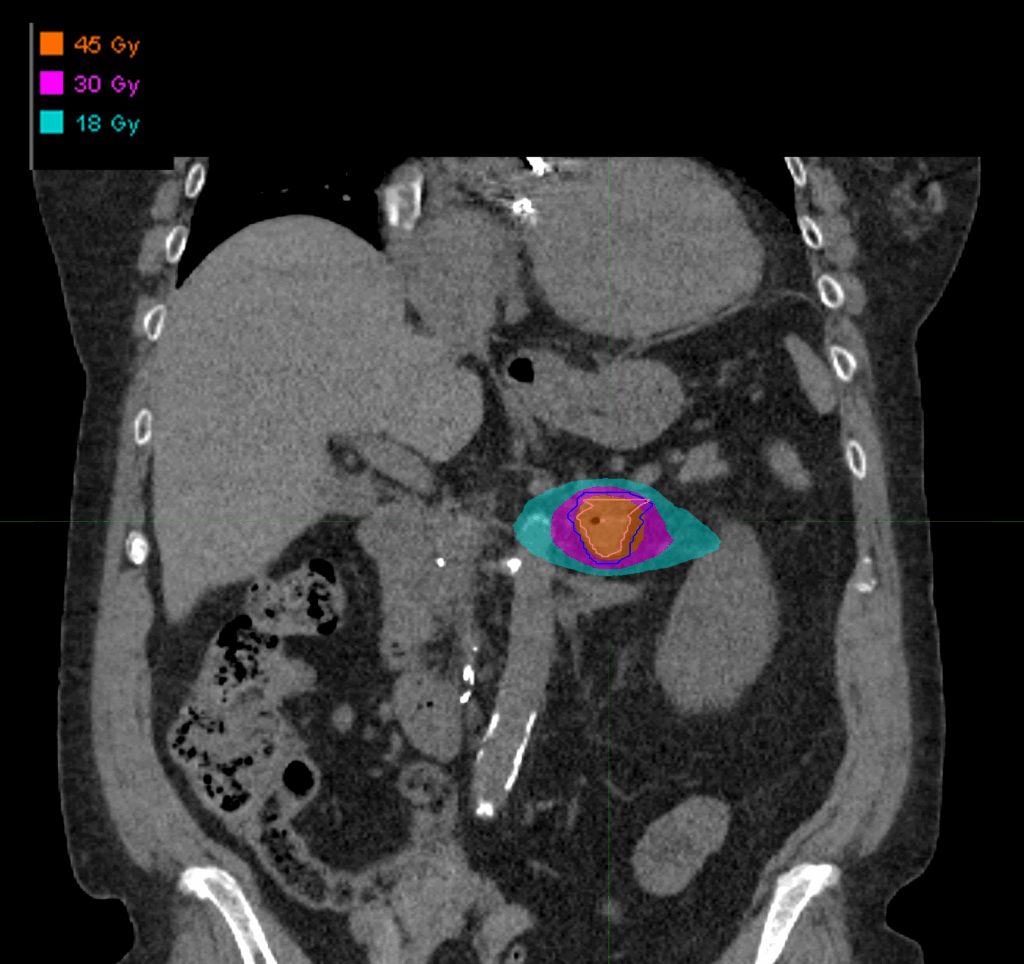

Treatment Plan Images

PTV(s) Volume

PTV, 14.7 cc

Dose Distributions

- Prescription to the 76.1% isodose line

- Max. dose 59.13 Gy